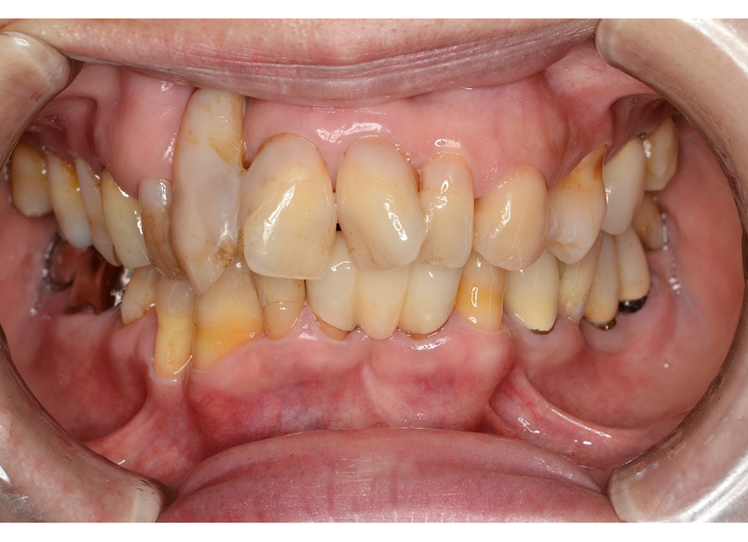

重度歯周病

(重度歯周炎)とは

歯周ポケットの深さが6~7mm以上となり、歯を支える顎の骨は大幅に溶かされてしまい、歯が抜けてしまうリスクが高まっている状態です。

重度歯周病になると歯周組織の著しい破壊が進みます。歯を支えている骨は2/3以上が溶け、支えを失うことで歯がグラグラと揺れるようになります。

臼歯の根分岐部(奥歯の根の分かれている部分)にまで組織破壊が進むと治療はより複雑になり、根分岐部の破壊が3/4以上進むことで歯が上下に動くようになると、一般的に歯の保存が困難となります。

重度歯周病に

よく見られる自覚症状

- 歯茎が真っ赤に腫れて

膿が出る - 歯周ポケットからの出血が

ひどくなる - 歯が上下左右に激しく

グラつく - 食事の際には痛みで噛めない

こともある - 歯がさらに下がる

(長くなったように見える) - 歯と歯の隙間が目立つようになる

- 口臭を強く感じるようになる